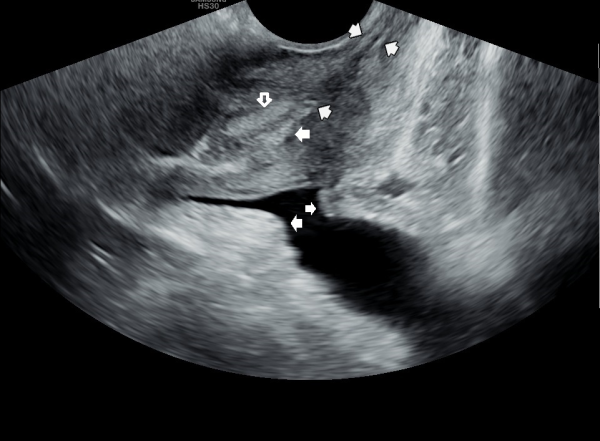

내원 첫날 정면 경직장 전립선 초음파 정낭의 검사상 사정관 입구의 순환 장애로 정낭의 낭종이 관찰되는 초음파 사진입니다.

This is a transrectal prostate ultrasound image taken on the first visit, showing a cyst in the seminal vesicle caused by a circulation blockage at the entrance of the ejaculatory duct.

4개월 가량 주 2회 정낭의 표적 치료후 정낭의 낭종들이 감소하고 순환되는 추적 경직장 전립선 초음파 사진입니다.

This is a follow-up transrectal prostate ultrasound image taken after approximately four months of twice-weekly targeted treatment of the seminal vesicles. The image shows that the cysts in the seminal vesicles have decreased and circulation has improved.